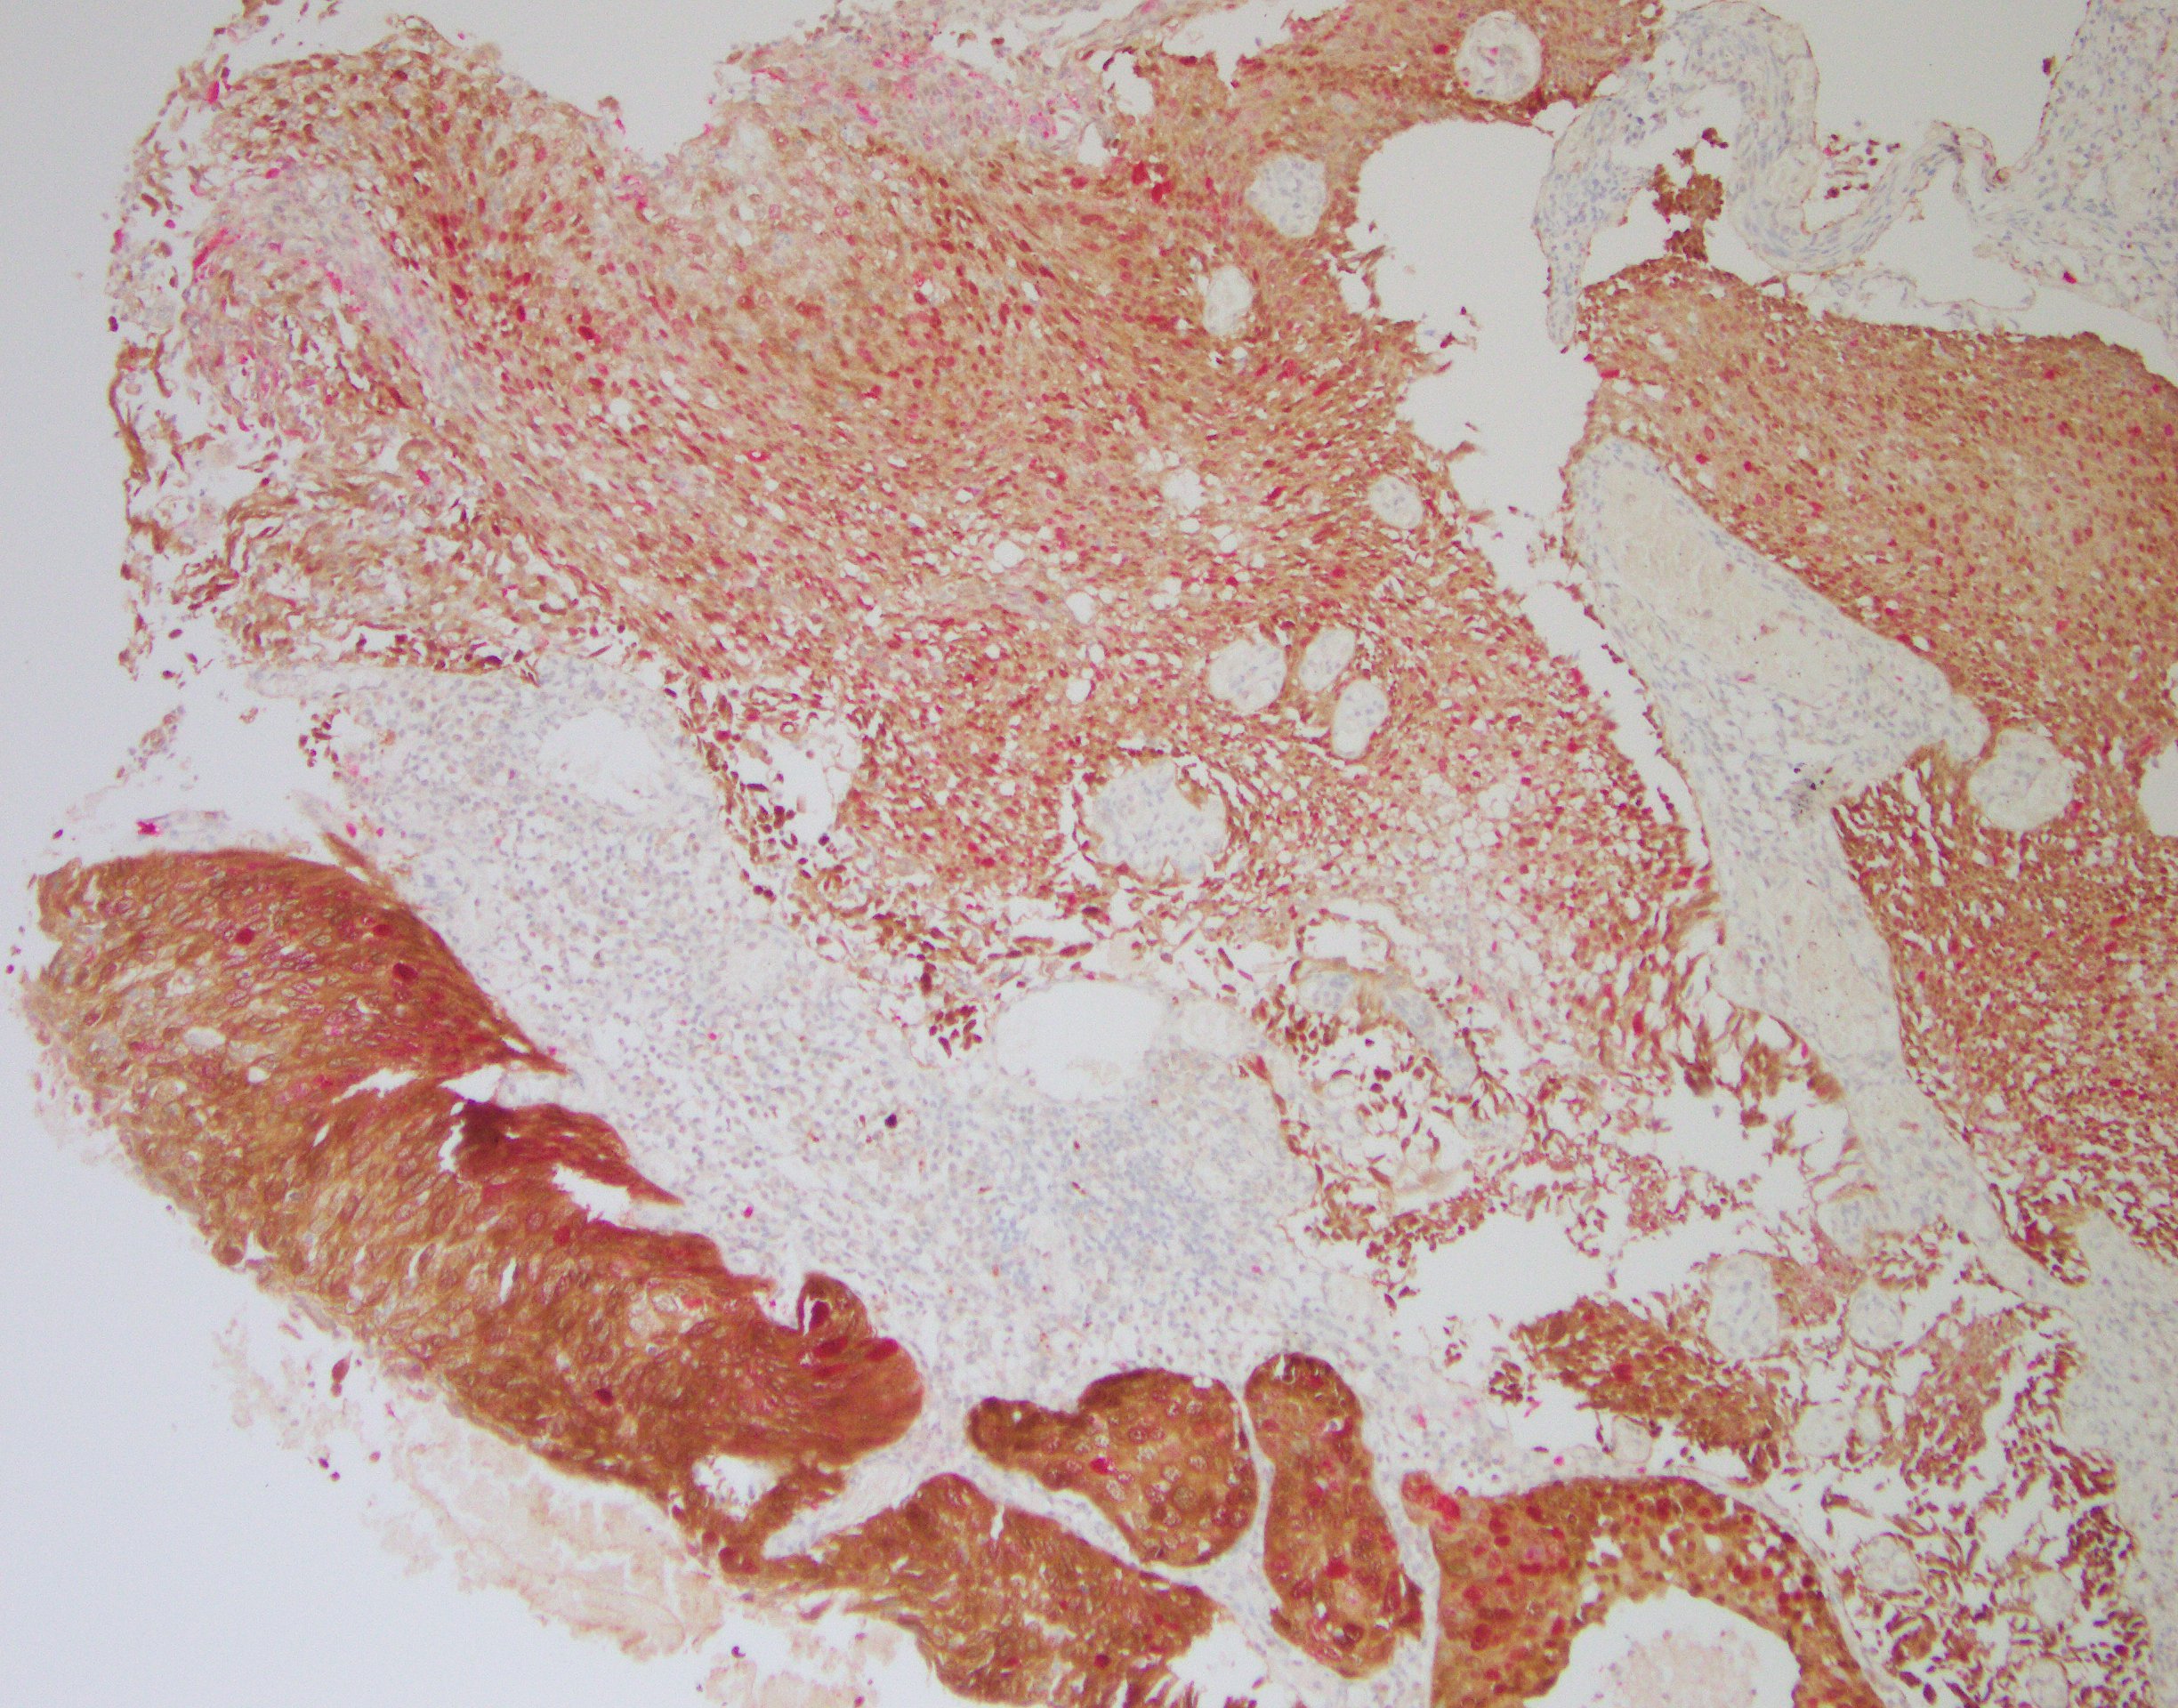

本试剂基于免疫组织化学检测原理:组织经抗原热修复处理后与一抗试剂(p16/Ki-67)进行孵育,在原位形成目标抗原-抗体复合物;抗原-抗体复合物中的 p16 抗体与辣根过氧化物酶(HRP)标记的聚合物二抗孵育结合,通过催化二氨基联苯胺(DAB)在细胞浆/细胞核上形成棕色沉积物;抗原-抗体复合物中的 Ki-67 抗体与碱性磷酸酶(AP)标记的聚合物二抗孵育结合,通过催化 AP 显色液在细胞核上形成玫瑰红色沉积物。光学显微镜下通过观察细胞的染色情况来确定是否存在目标抗原的表达。

高级别CIN组织,p16/Ki-67双染